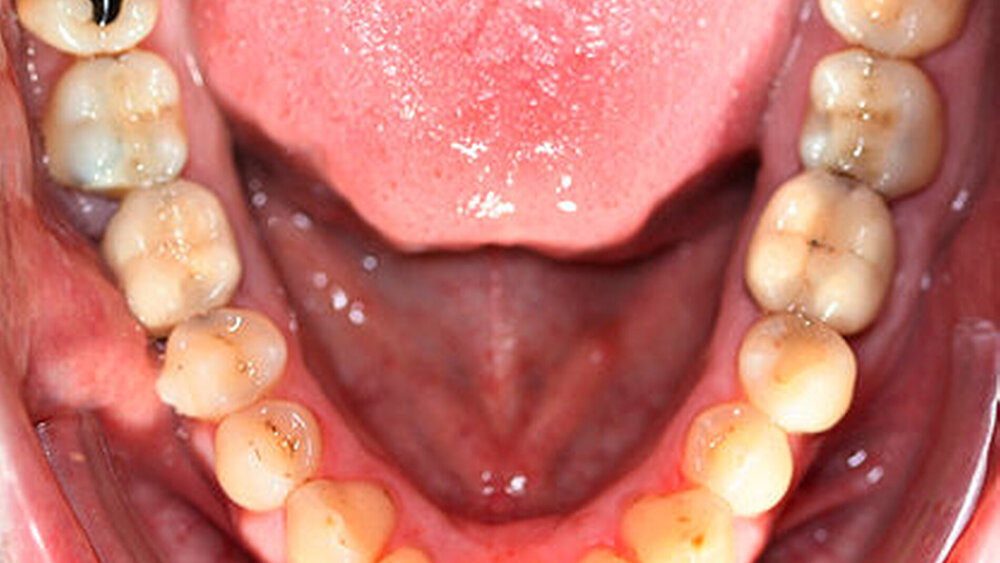

Die Sulkustiefen konnten auf etwas weniger als 4 mm reduziert werden, während der Blutungs- und Plaque-Index bei weniger als 15 Prozent lag. Daher wurde eine kieferorthopädische Behandlung über die nächsten zwei Jahre in Kombination mit engen zahnärztlichen Kontrollen geplant. Als Mittel der Wahl entschieden wir uns gemeinsam mit dem Patienten für das Invisalign-System, da hiermit sowohl eine Schienung als auch eine kraft-arme Bewegung der Zähne möglich sein sollte. Für den Frontzahnbereich wurden keine Attachments geplant, so dass hier eine unnötige Hebelwirkung umgangen werden konnte (Abbildung 3).

Um einen kompletten Lückenschluss im Oberkiefer zu ermöglichen, musste im Unterkieferfrontzahnbereich zusätzlich zur Derotation und Positionierung der Zähne – insbesondere Zahn 41 – von approximaler Schmelzreduktion, kurz ASR , Gebrauch gemacht werden, um einer Tonn`schen Diskrepanz entgegenzuwirken (siehe dazu Abbildung 7 auf Seite xy).